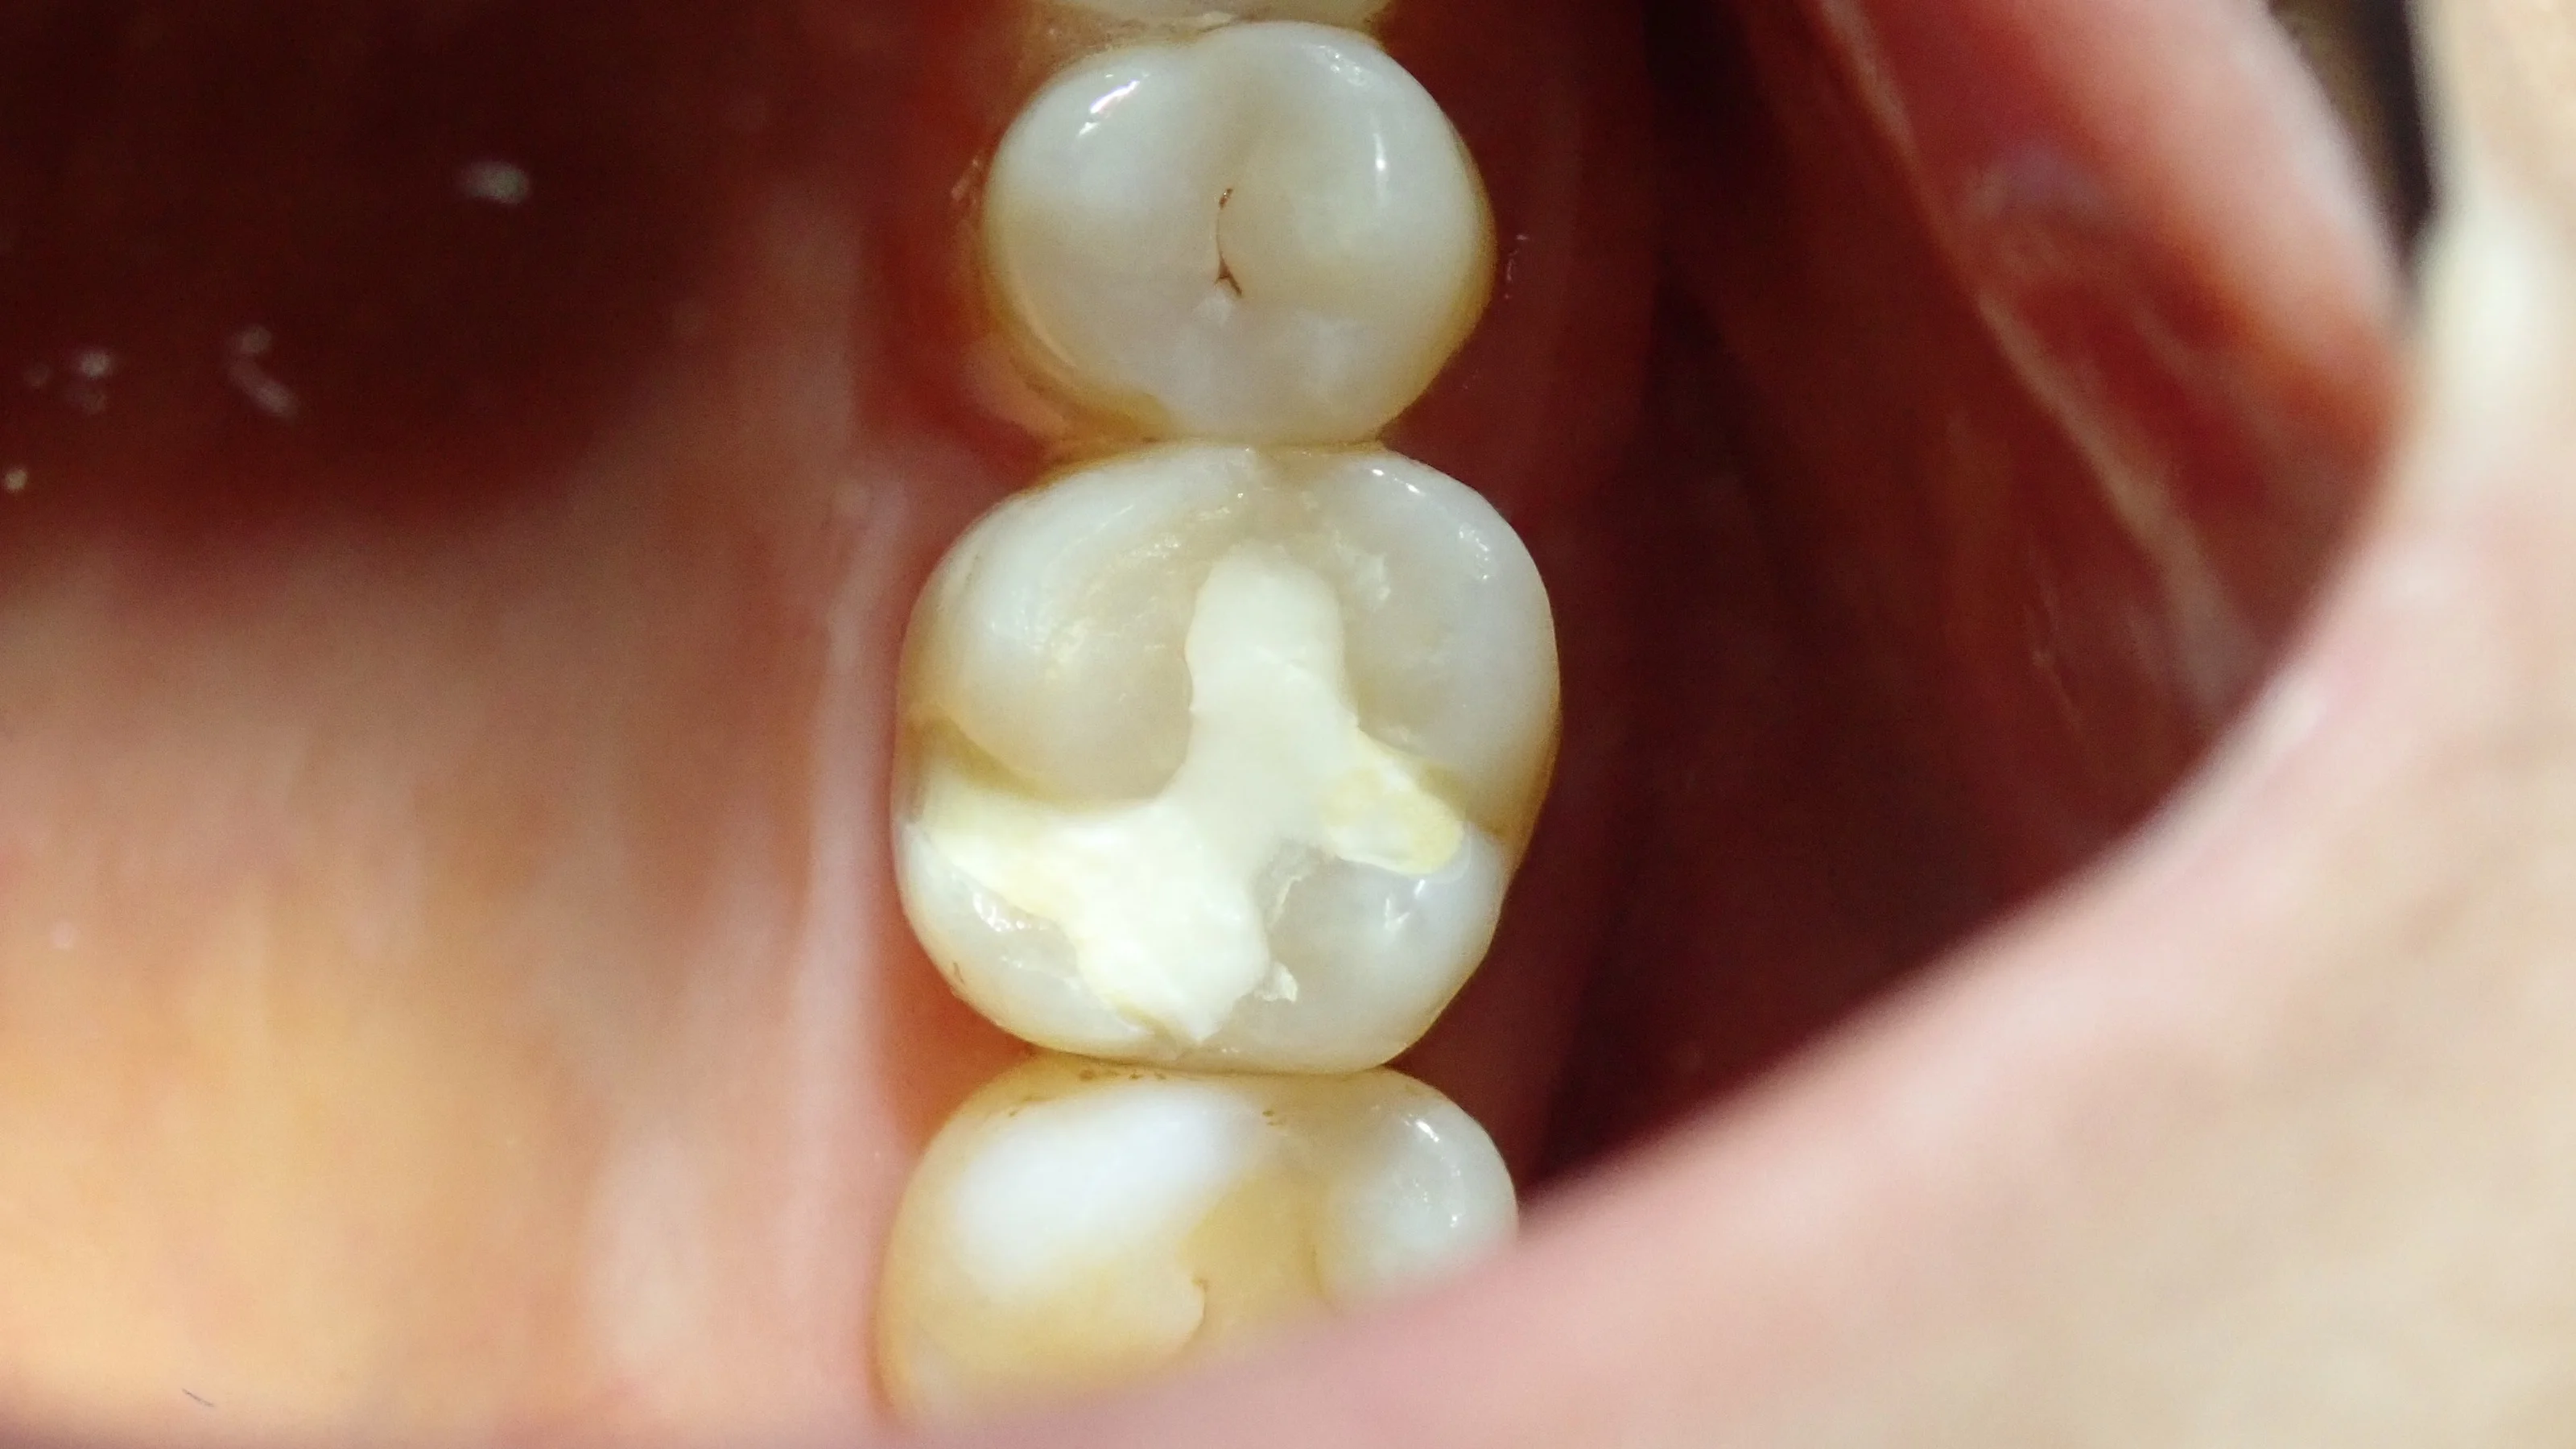

術前です。

白い部分は仮封材 (いわゆる仮の蓋)が入っており、虫歯は既に取り切っている状況です。

私はよく「虫歯だけ取って、次回最終的なものの型取り・詰める」といった処置をします。

専門用語だと「覆罩」と呼ばれる処置です。